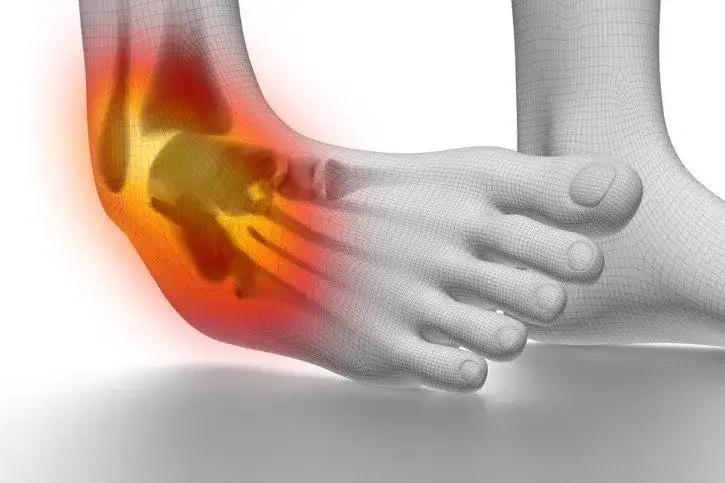

Czy skręcenie kostki boli? Poznaj rodzaje bólu i leczenie

Czy skręcenie kostki boli? Dowiedz się, jakie są objawy bólu, jego intensywność oraz skuteczne metody leczenia i rehabilitacji.